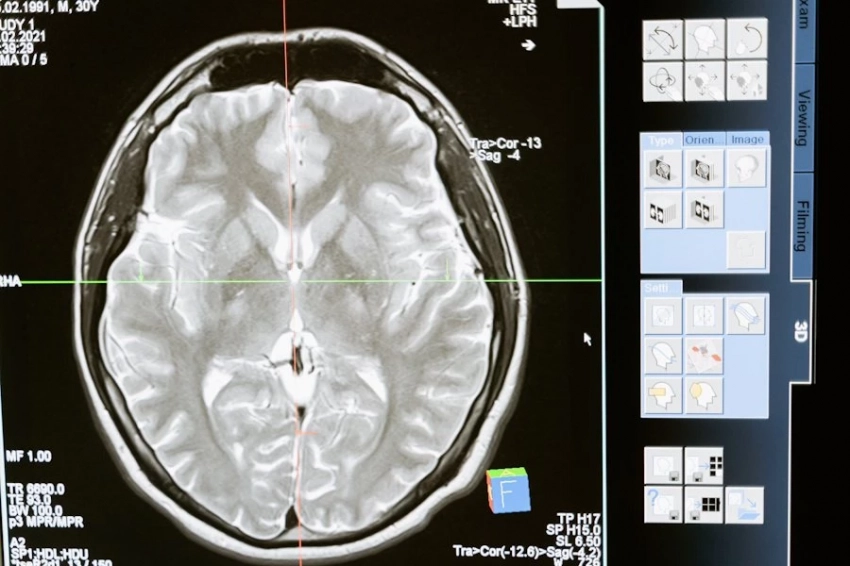

Академик Пирадов о достижениях ученых РФ по улучшения работы мозга

Российские ученые достигли значительных успехов в улучшении работы мозга, разрабатывая методы для стимуляции памяти и защиты от нейродегенеративных заболеваний, рассказал Академик РАН Пирадов изданию "КП".